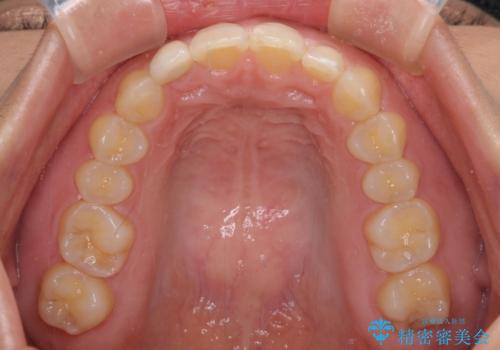

- 前歯の空隙と矮小歯を気にして来院された患者様です。

上下の歯列不正はインビザラインにより整えることとしました。

矯正治療の後に、前歯1歯と奥歯をオールセラミックにて治療することとしました。

矯正治療により矮小歯前後にスペースを作りながら歯列を整え、セラミッククラウン装着後に最終的に歯列と咬合を仕上げました。